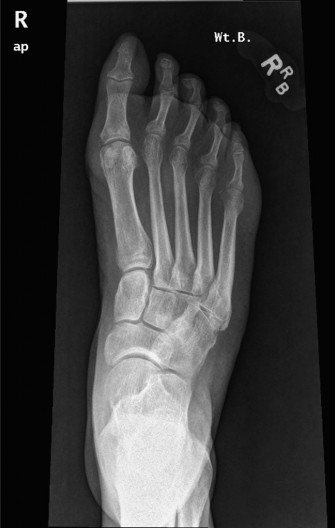

A 54-year-old male presents with right forefoot pain, swelling, and a sense of pressure. He reports that he w…